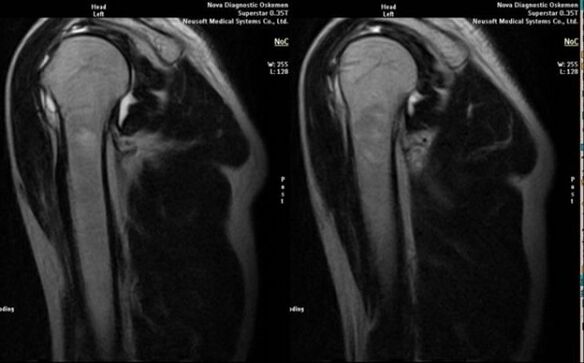

- magnetic resonance imaging and computed tomography;

Signs that directly indicate the development of arthrosis include the appearance of significant narrowing of the joint space, sclerosis of subcartilaginous structures, thinning of the chondrocyte layer itself, appearance of osteophytes and deposition of salt crystals in the intra-articular fluid.